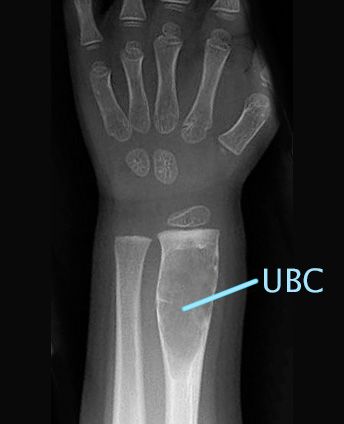

X-ray of unicameral bone cyst on wrist

A unicameral bone cyst shows up clearly as a dark spot in this X-ray of the radius (wrist).